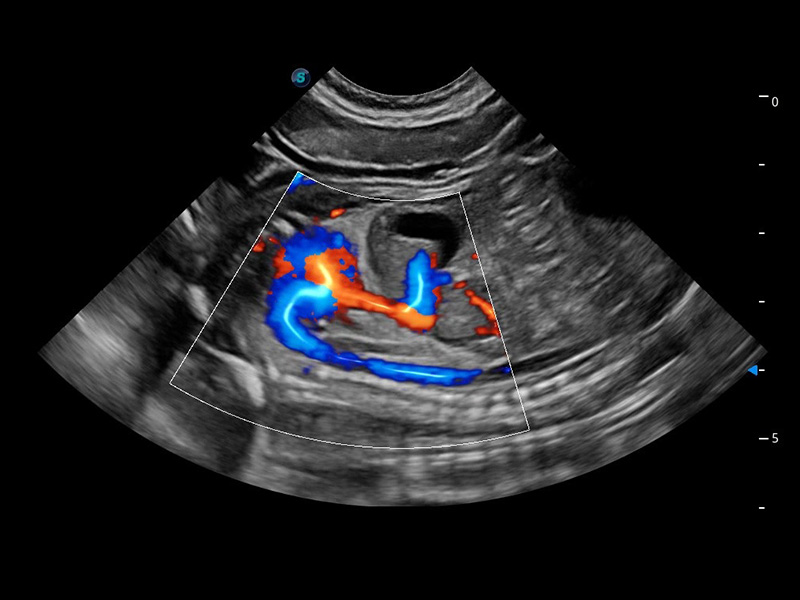

ProPet 60 作为一款高端台式动物超声设备,为动物医生的日常诊断提供了一系列贴合动物临床需求、解决临床实际问题的高级成像功能。凭借全系列高清探头,满足医生对腹部、心脏、生殖、浅表、肌骨等成像的所有需求,切实帮助您提升检查效率,提高诊断信心。

兽用彩色多普勒超声诊断系统

动物是人类最亲密的朋友和最值得信赖的伙伴。云顶集团官网也一直致力于探索动物专用的超声影像解决方案。 全新推出的ProPet系列,是云顶集团官网在动物超声影像智能化、专业化、精准化的一次跨越式革新。动物不能用言语来表述自己的不适,通过超声影像,ProPet系列搭建了动物医生与不同物种沟通的“桥梁”,为动物医生注入了“治愈之力”。